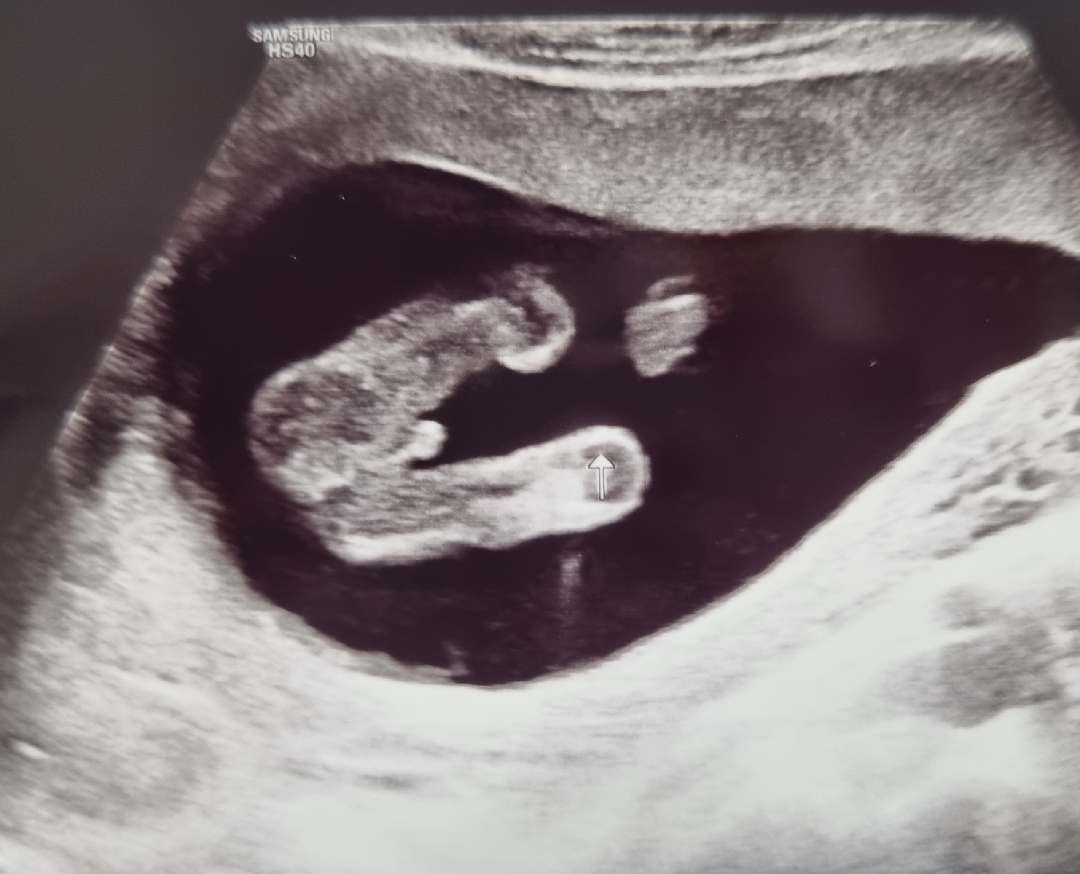

15주차 성별 봐주세요~

탯줄 아니겠죠?!? 제눈에는 🌶 같은데

남아같아요

제 눈에도 🌶같아요!